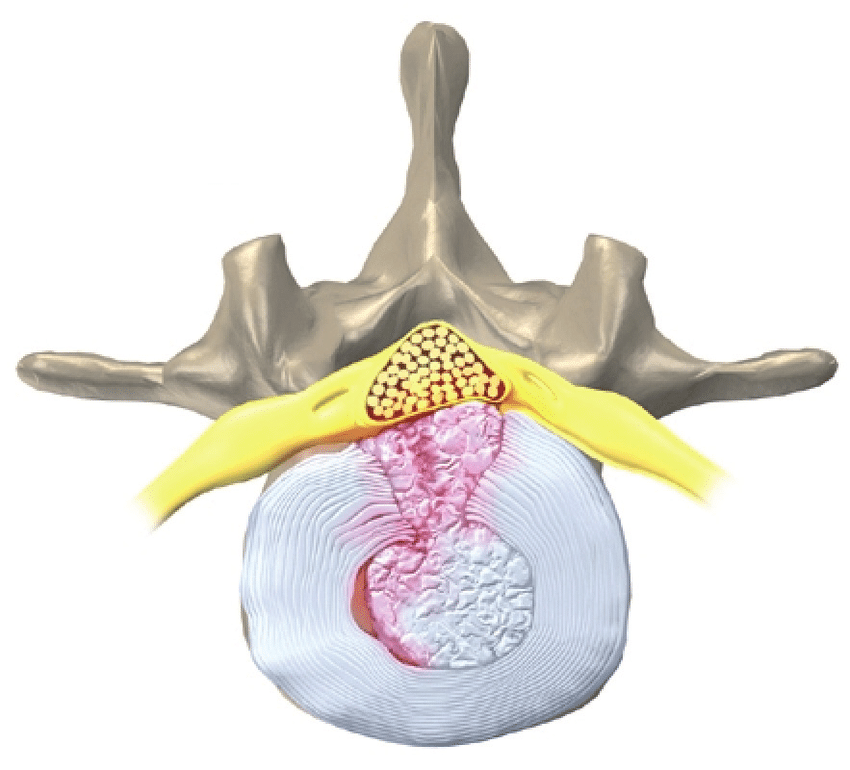

• El síndrome de conus medullaris se debe al daño en el extremo de la médula espinal por encima de la mayor parte de la cauda equina y, por lo tanto, en un nivel más alto de la columna. (El síndrome del cono medular se refiere a la disfunción de la porción cónica más distal de la médula espinal, que anatómicamente se encuentra aproximadamente en el nivel de la columna vertebral T12-L1). conus medullaris en sí, especialmente por tumor. El síndrome del cono medular por lo general progresa más rápidamente, se asocia con dolor de espalda más temprano y alteración del esfínter, y es más probable que se asocie con la preservación de algunos reflejos de las extremidades inferiores, por lo general rotuliano.

• Las lesiones de la columna lumbar pueden dañar el cono medular, la cauda equina o ambos. El síndrome de cola de caballo es la compresión de las raíces nerviosas por debajo de la terminación de la médula espinal. La disfunción de la raíz nerviosa se debe a la compresión directa de las estructuras circundantes. Las causas importantes incluyen trauma agudo; enfermedad ósea degenerativa crónica con retropulsión de fragmentos en el canal espinal; enfermedad del disco lumbar; infecciones como abscesos; tumor intraespinal y meníngeo; y hematoma intraespinal. Este síndrome puede ser una complicación rara de los procedimientos espinales menores y mayores. El síndrome de cauda equina generalmente se desarrolla como un proceso crónico insidioso a menos que se deba a un traumatismo agudo. Los síntomas pueden incluir dolor de espalda, dolor en las piernas, debilidad y calambres en las piernas. Los síntomas sensoriales pueden ser pérdida sensorial (anestesia en silla de montar) y dolor neuropático. La alteración del esfínter es común, especialmente con la progresión.